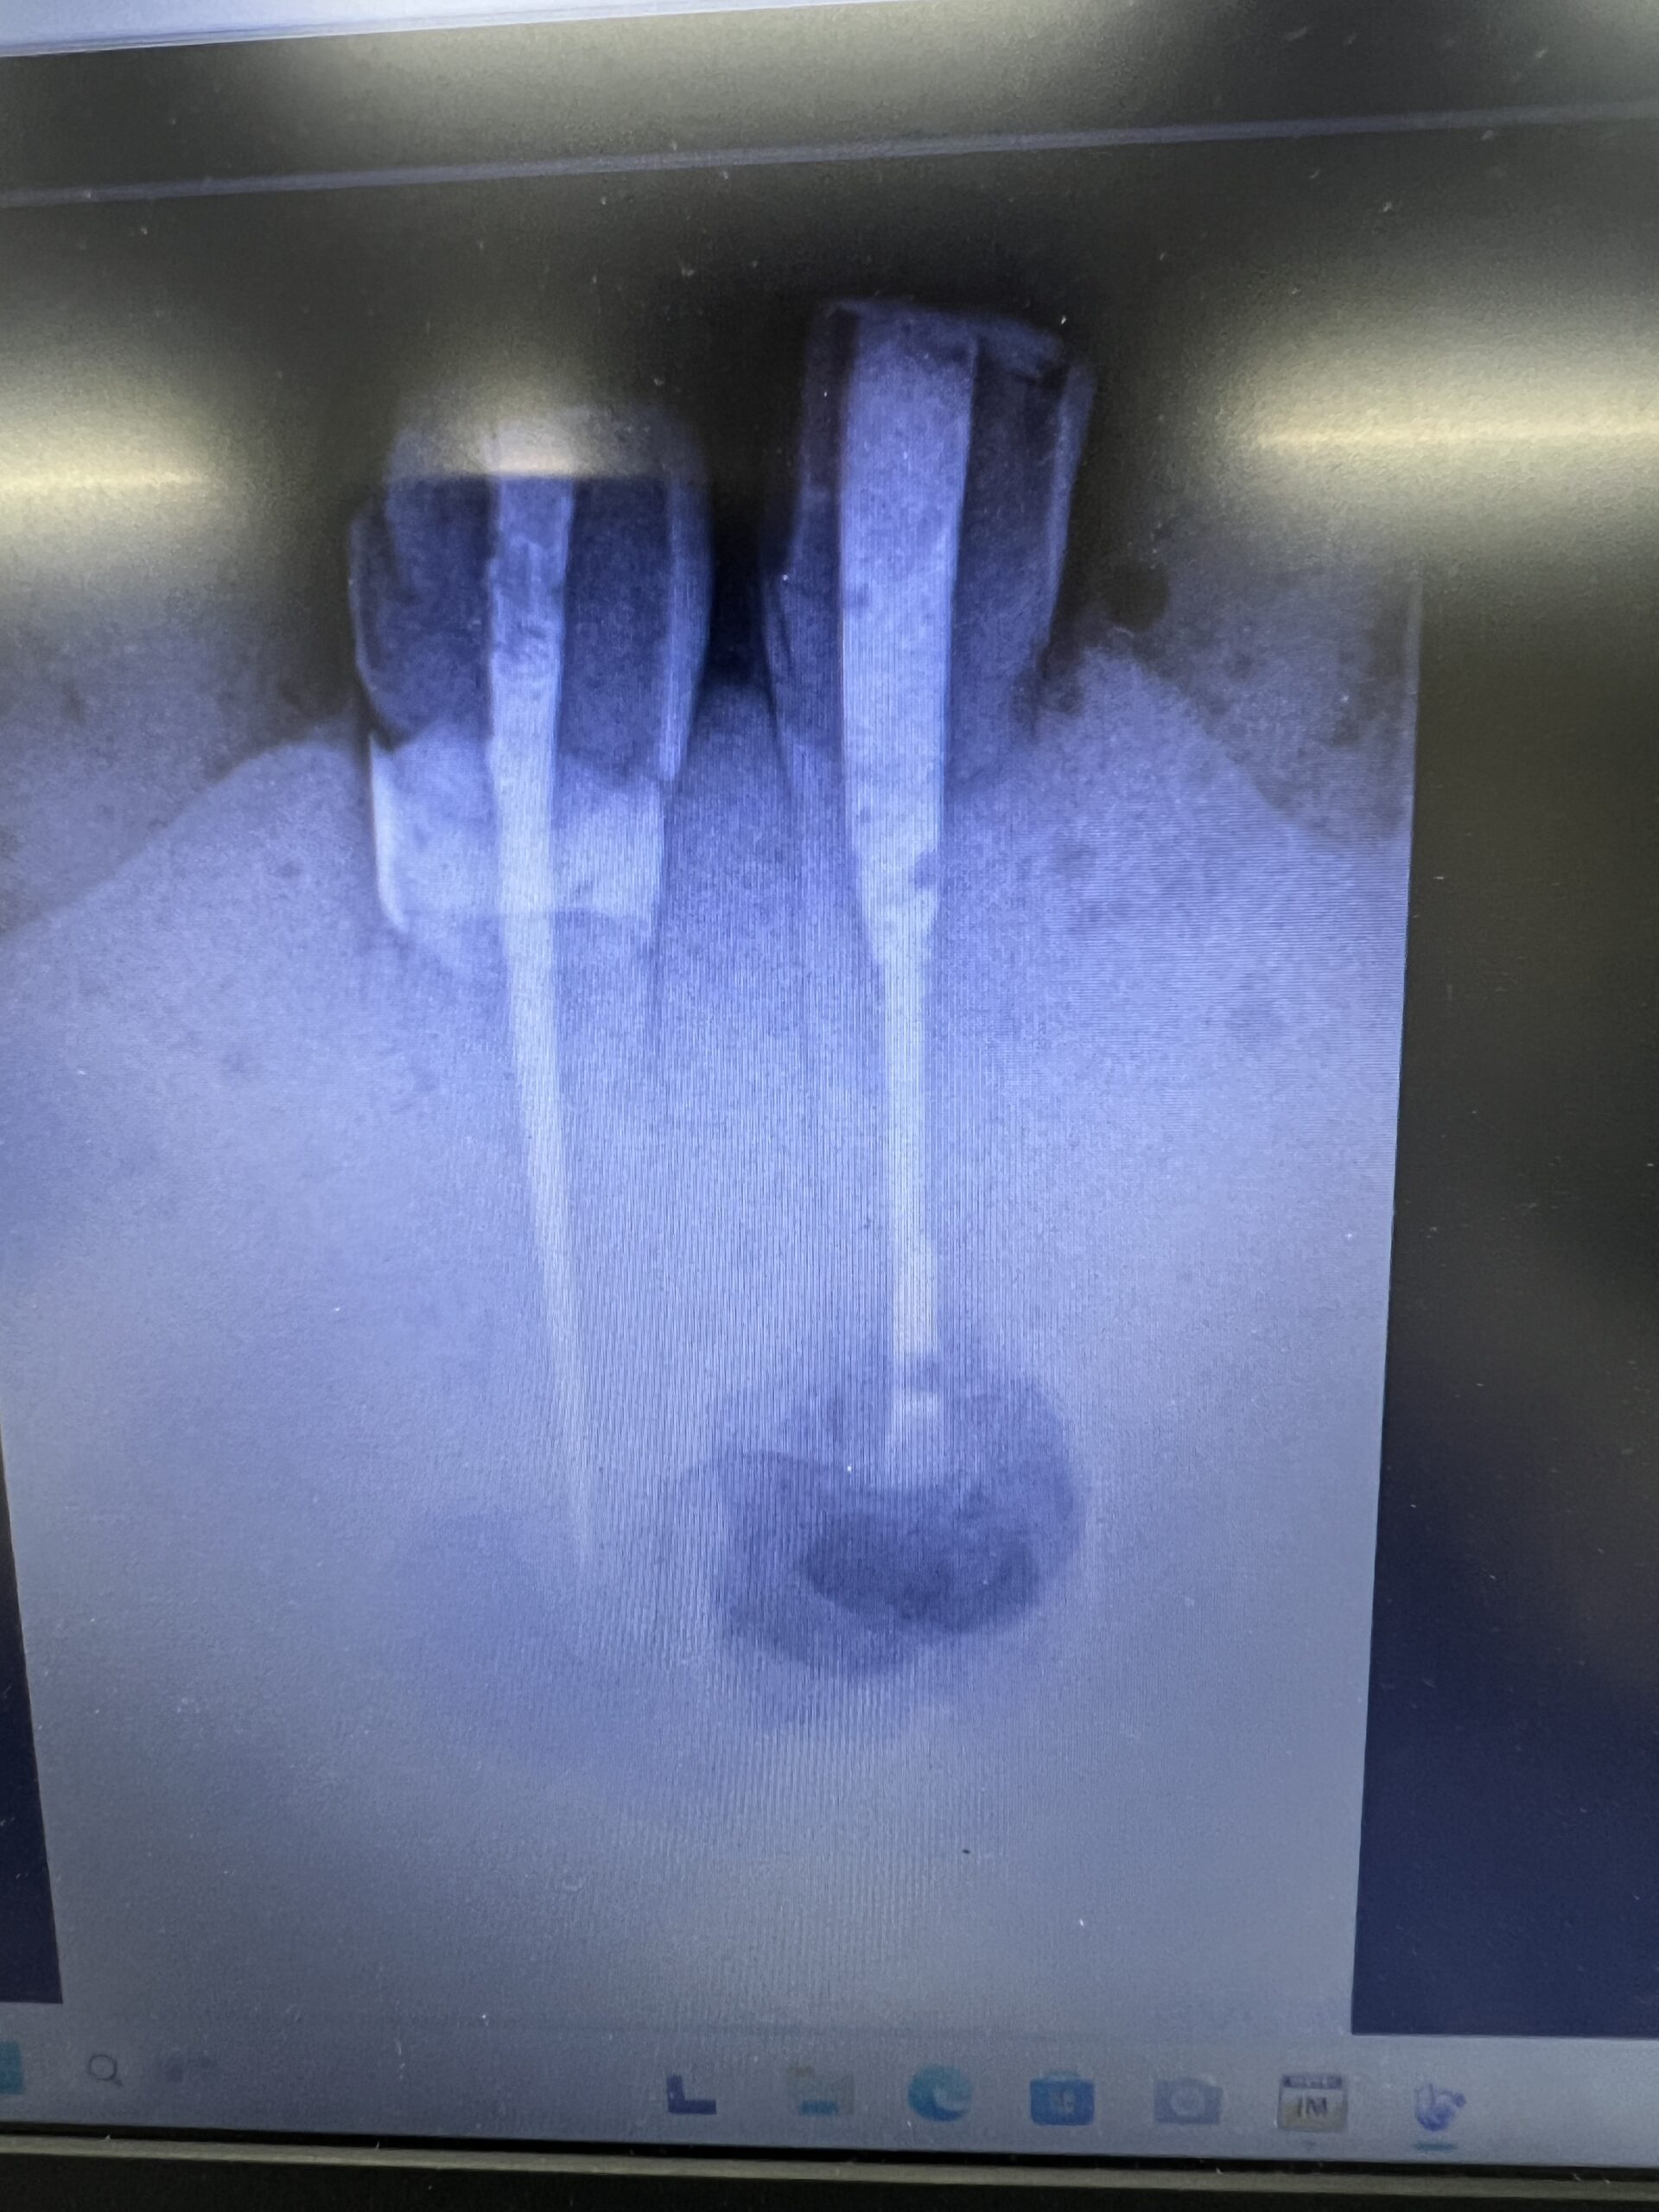

ここで、撮影をしてもらったCBCTを公開しよう。以下である。

Intentional Replantationも問題なくできている。

次の受講者は以下だ。